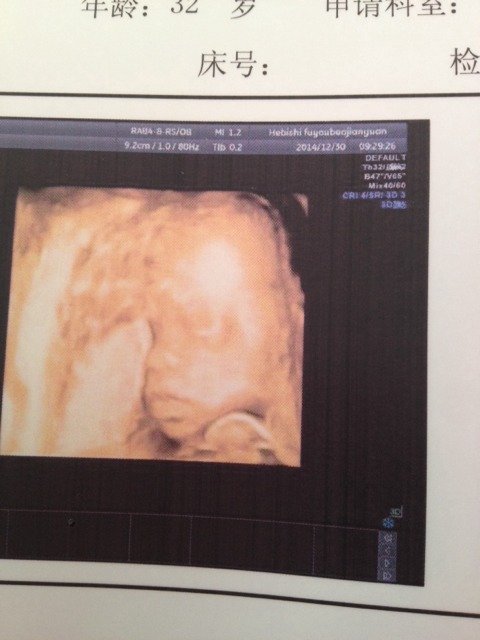

我发现我宝四维照片不那么丑了!刚开始感觉那么丑 我发现我宝四维照片不那么丑了!刚开始感觉那么丑 点击展开 珊珊珊 2015-02-09 00:34 为您推荐: 其他回答 因为是在你肚子里 被羊水包围着 没有光线 一出生有外围环境了 自然就好看了 ˵İ999 2015-02-09 12:49 宝宝生下来会很漂亮的 非常张小沫 2015-02-09 10:13 还好啊... 萌$_$宝 2015-02-09 07:03 都是会变的 没有没有 2015-02-09 03:05 越看越美, 爺.請珍惜我 2015-02-09 01:59 加载更多 相关问题 宝宝6个月的四维照片很丑怎么办 四维的照片不漂亮,宝宝生出来能漂亮吗